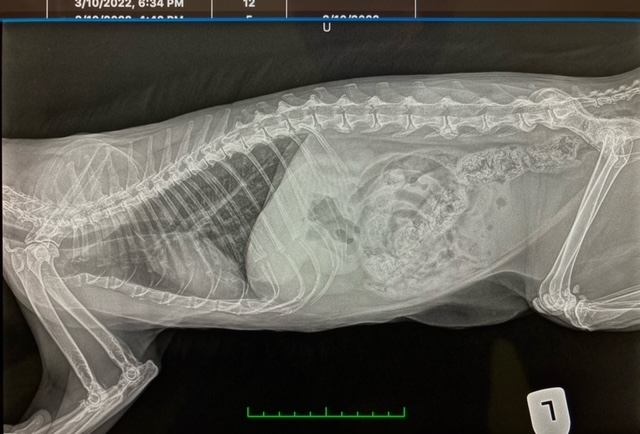

數碼X光

當診斷身體內部問題時,X-光是其中一種最有效快捷的工具。我們診所擁有最先進的數碼X-光協助診斷有問題的地方和嚴重性,包括骨折、腫瘤、膀胱石和腸胃裡的異物(衣物,骨頭、玩具)等。X-光也可幫助我們診斷心臟和肺部問題,也可以用作評估身體骨骼發展,例如狗隻的臀部和手肘發育異常。由於您的寵物需要最佳的診斷服務,我們經驗豐富的獸醫會評估和為您解釋您寵物的X-光圖像。數碼X-光比一般X-光更清晰準確,這令您的寵物可得到更準確的治療。這些圖像將被保存到電腦病歷或如果需要,會轉交專家硏究。數碼X-光不會產生化學廢物,對環保也有幫助。